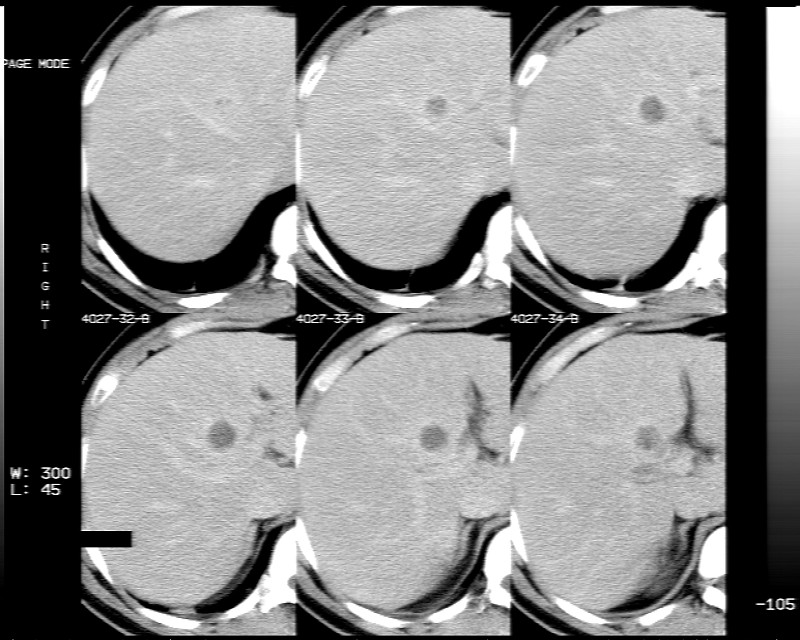

男性,52岁,腹痛,无发热,生化检查无明显异常,既往有胰腺炎病史,经治疗好转出院。

胆囊炎,肝脓肿(周围可见异常灌注)

1)考虑肝左叶内侧段肝脓肿,不排除转移瘤。2)脂肪肝。3)慢性胆囊炎。4)十二指肠降部肿瘤可能。

胆囊炎、脂肪肝、肝脓肿。